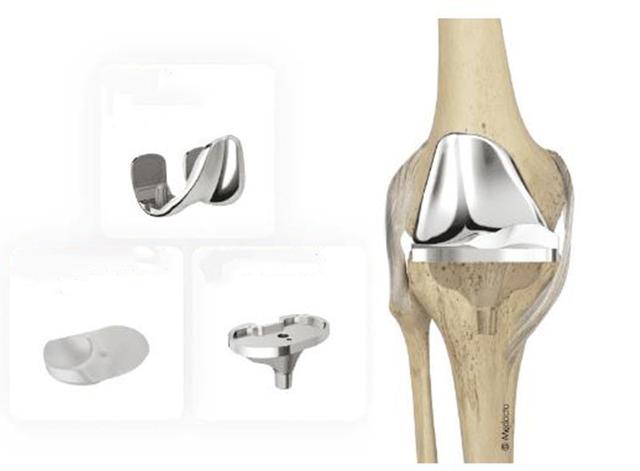

• 换膝盖要花多少钱?膝关节置换手术的优点有哪些?

膝关节位于大腿骨和小腿骨连接处,健康的膝关节能够自由地活动,是因为关节表面覆盖一层滑润的软骨组织和关节周围有强健的肌肉。 软骨是一层光滑的软组织,它覆盖在大腿骨和小

• 膝关节置换手术要花多少钱?关于这台手术你要了解的还有很多……

当所有非药物和药物疗法都无效,骨关节炎已经发展到晚期,患者遭受持续严重的关节疼痛和功能障碍时,可考虑进行关节置换术。医生会根据患者的年龄、体重、活动水平、膝关节大小,形状以及整体健康状况制定手术方案,也不一定换掉整个关节,也可换掉一部分关节(单髁关节置换术),大部分患者手术次日就可下地先走,康复后可很大程度的恢复日常功能和生活质量。不过人工关节毕竟有使用寿命,因此骨关节炎的治疗原则是:从保守无创治